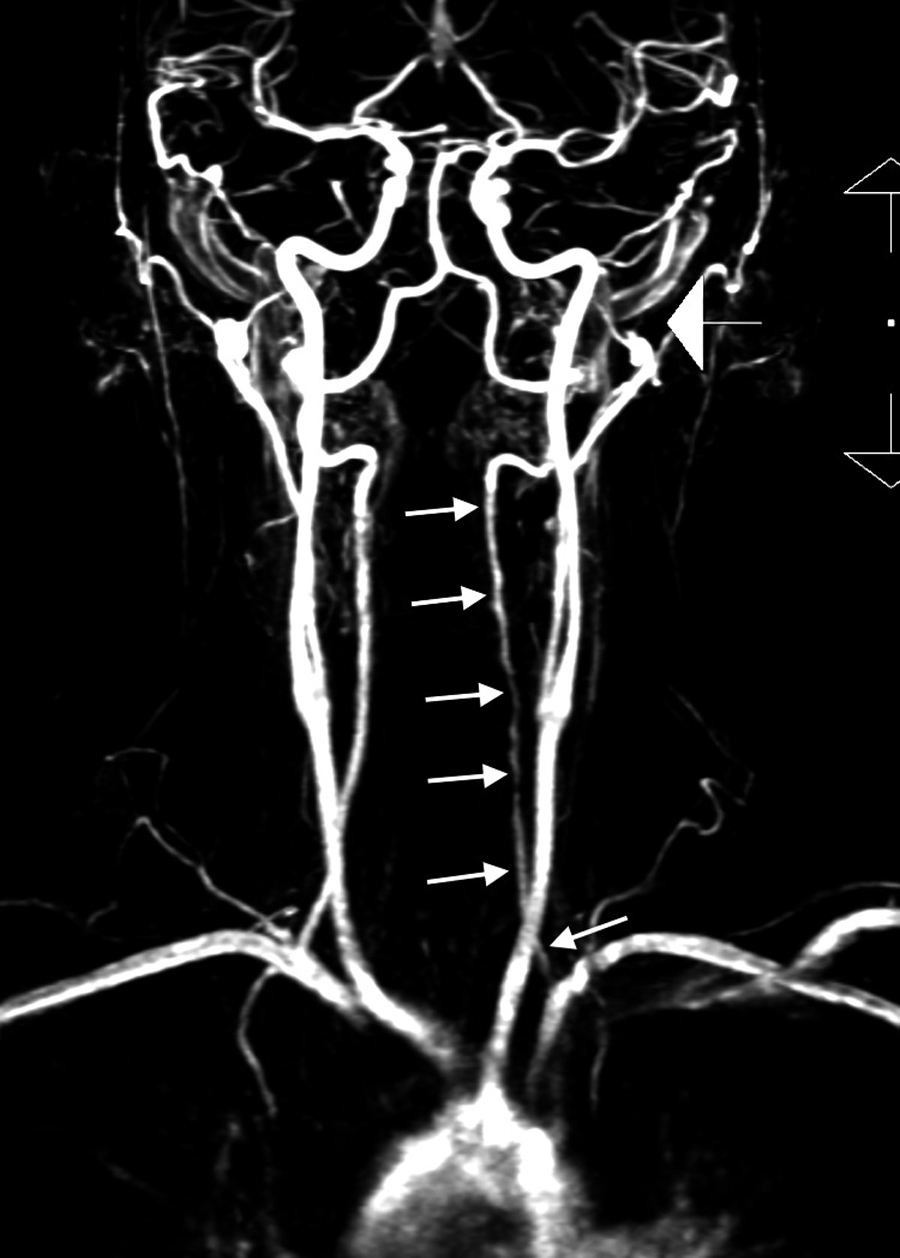

An attending neuroradiologist read the MRA study of the neck. The imaging protocol included an unenhanced two-dimensional time-of-flight axial MRA with multiplanar reformations, supplemented by an unenhanced axial T1-weighted fat-saturated sequence. Additionally, contrast-enhanced coronal MRA of the neck with multiplanar reformations was obtained. The neuroradiologist noted that an irregular contour was observed throughout the majority of the V2 segment of the left vertebral artery. On axial T1-weighted fat-saturated images, a crescentic intrinsic hyperintense signal was noted surrounding this segment, consistent with intramural hematoma, diagnostic of arterial dissection. The radiologist’s report reflected a long segment dissection of the left vertebral artery of the V2 segment, without evidence of hemodynamic compromise.

Follow-up (day 31)

At the request of the attending out-of-state chiropractor, an independent review of the MRA studies was subsequently performed by a fellowship-trained neuroradiologist, who provided additional interpretive findings. The neuroradiologist confirmed the presence of a large, long-segment dissection of the left vertebral artery extending from the origin at the aortic arch through the V3 segment (Figure 1). An associated intramural hematoma was visualized with an intra-arterial filling defect located in the V2 segment of the left vertebral artery (Figure 2). Luminal narrowing of approximately 70–80% was noted, with hyperintense signal characteristics of the intramural hematoma (Figure 3), consistent with an early subacute-late subacute phase, suggestive of a dissection occurring within the preceding 14 days. [12] At the V3 segment, both a central lumen and a false lumen were visualized, indicative of active intramural dissection with differential arterial flow dynamics (Figure 4).

These detailed imaging findings were thoroughly discussed with the patient. One month later, the patient remained stable and was scheduled for follow-up with both a neurologist and a neurovascular surgeon. The chiropractor recommended further rheumatologic and genetic testing to refine the diagnosis and evaluate for a potential heritable connective tissue disorder and predispositions for recurrent dissections. The timeline of the case is summarized in Figure 5.